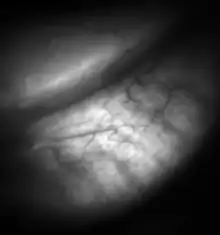

![Meibomian glands in the lower eyelid imaged under amber light to show vasculature support and the gland structure [epiCam].](../I/Meibomian-glands.png.webp)